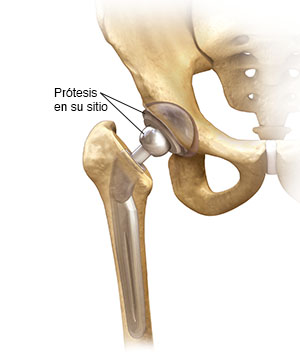

La cirugía de reemplazo total de cadera casi siempre disminuye la cantidad de dolor en la articulación. Durante esta operación, la articulación de la cadera que tiene el problema se reemplaza por una articulación artificial, denominada prótesis.

Cuando el equipo de cirugía esté listo, lo llevarán al quirófano. Allí le aplicarán anestesia. La anestesia lo ayudará a dormir durante la cirugía o lo insensibilizará de la cintura para abajo. A continuación, el cirujano le hará una incisión para obtener acceso a su articulación de cadera. Le quitarán la cabeza del hueso (esfera) dañada y le prepararán la cavidad para colocar la prótesis. Una vez que la nueva articulación esté en su sitio, le cerrarán la incisión con grapas o puntos.

Preparación del hueso

La cadera es una articulación formada por una cabeza (ball) y un hueco (socket). Se corta la cabeza del fémur (hueso del muslo) y se alisa la superficie de la cavidad antigua. A continuación, se coloca la nueva cavidad en la pelvis. Generalmente, la cavidad se encaja a presión y se mantiene en su sitio con tornillos. Las prótesis de encaje a presión contienen diminutos poros en la superficie, que permiten que crezca hueso en su interior. Para sujetar la parte de la prótesis formada por la esfera y el vástago puede usarse encastre a presión o cemento.

Unión de las nuevas partes

En la parte superior del fémur, se introduce el nuevo vástago de la articulación de cadera. Una vez que el vástago esté bien fijo al fémur, se conecta la nueva esfera a la nueva cavidad. El vástago de la prótesis puede fijarse con cemento, o bien ser de encaje a presión. Su cirujano elegirá el método más adecuado para su caso.